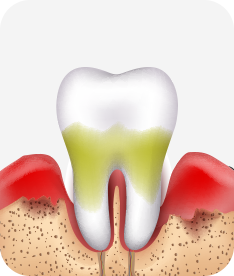

치주염 (말기)

잇몸이 항상 부어 있으며, 이가

흔들리는 정도가 점점 심해짐.

치주치료가 필요하며, 정도에 따라 치아를 발치하여야 할 수 있음.